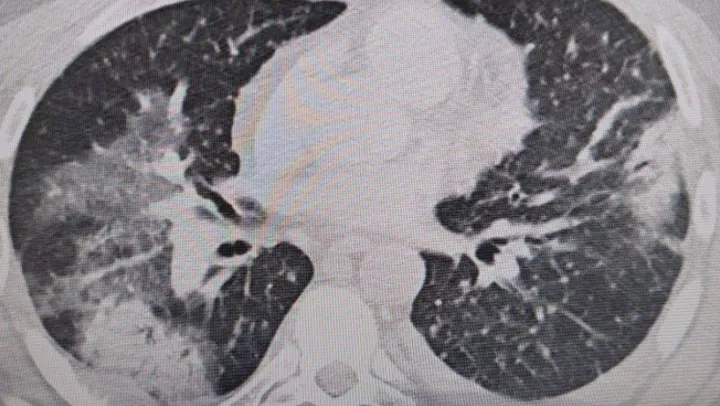

Bu yazın tüm Türkiye'de sıcak ve nemli olması ve klima kullanımının da artması bekleniyor. Hem ev hem işyerlerinde serinlemek için açılan klimalar ve havalandırmalar yaz aylarında en sık görülen ve halk arasında "zatürre" olarak bilinen pnomoniye neden oluyor. Altınbaş Üniversitesi Tıp Fakültesi, Göğüs Hastalıkları Anabilim Dalı Başkanı Prof. Dr. Şevket Özkaya, kış aylarında grip gibi hastalıklar daha fazla iken yaz aylarında ise bu tip zatürrenin daha sık görüldüğüne dikkat çekti.

Prof. Dr. Şevket Özkaya, “Legionella” bakterisinin klima sularında üremesiyle insanların yaz zatürresine yakalandıklarını ve kış aylarına göre çok daha fazla vakayla karşılaştıkları bilgisini verdi. Klima zatürresinin özellikle kronik rahatsızlığı olanlarda ölümcül olabileceğini belirten Prof. Dr. Şevket Özkaya önemli uyarılarda bulundu. Özkaya, “Klimaların havalandırılmasıyla beraber insanlar 'lejyoner' bakterilerini akciğerlerine aldığında 'klima pnömonisi' ya da 'yaz zatürresi' dediğimiz hastalığa yakalanıyorlar. Bunun özellikle kronik astım, KOAH ve kanser hastalarında ölümcül sonuçlar doğurabileceğini biliyoruz” dedi.

Özellikle klimaların iyi temizlenmesi gerektiğini ifade eden Prof. Dr. Özkaya, “Klima zatürresinde grip gibi belirgin değil. Eklem ağrıları, ateş, halsizlik, ishal gibi hafif soğuk algınlığı belirtileriyle seyrettiği için de hemen anlaşılmayabilir. Özellikle kronik hastalığı olanlarda hayati sonuçlar doğurabilir. Ani ısı değişiklerine, örneğin sıcaktan soğuya ve klimalara maruz kalmakla oluşan belirtiler korona ile de karışabilir. Vatandaşlarımız, özellikle kapalı yerlerde kendilerine dikkat etsinler. Klima ayarlarını 22 derecenin altına düşürmesinler. Özellikle de bu ısı değişimlerine uzun süre maruz kalmamalarını öneriyorum” şeklinde konuştu.